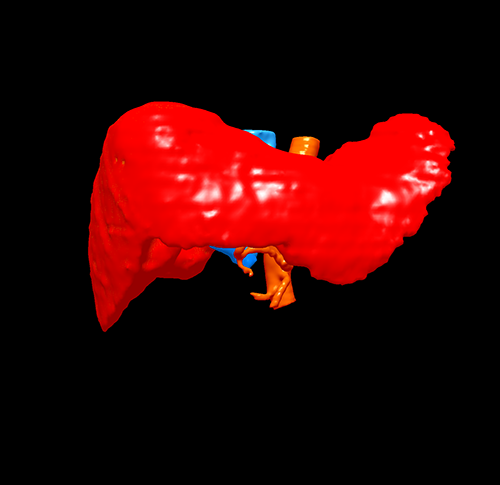

右肝肿瘤---右半肝切除